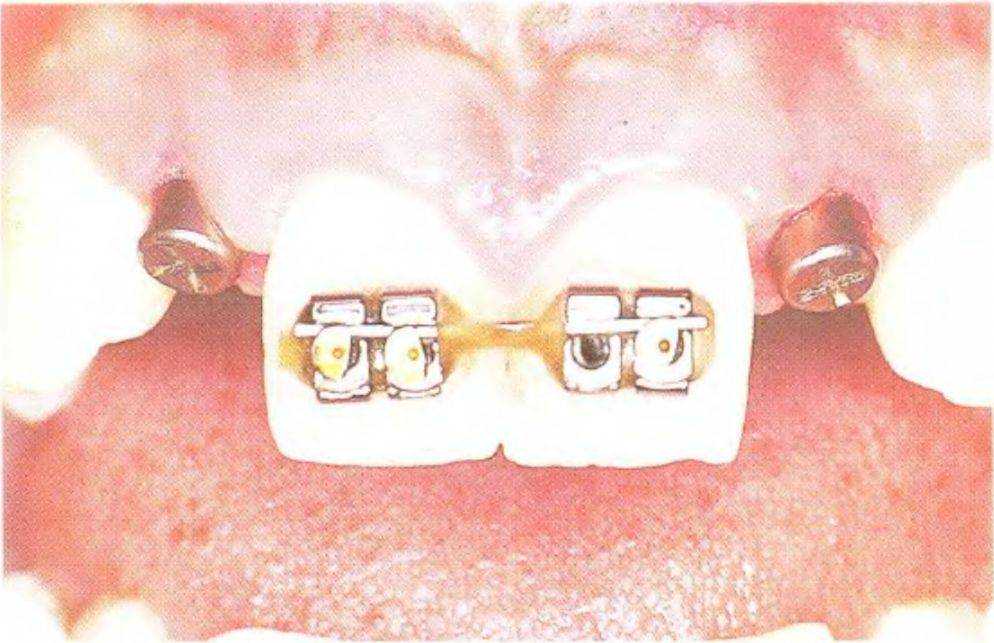

Рис. 3 39а. Пациентка 17 лет с отсутствующими латеральными резцами верхней челюсти

Рис. 3-39f. Устранение диастемы с помощью ортодонтического аппарата